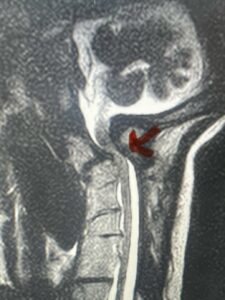

This is a 42 year-old female who presents with severe progressive weakness and numbness and difficulty with balance over a 6-month period. She has a history of having a motor vehicle accident at 5 years old but was never imaged. On exam she was noted to be severely myelopathic. Imaging revealed severe spinal cord compression at the level of C1 (Figs 4a and b).

Fig. 4a: Sagittal T2-weighted cervical MRI demonstrating severe cord compression with myelomalacia of upper cervical spinal cord (red arrow). Notice the increased atlanto-dens interval (red dot).